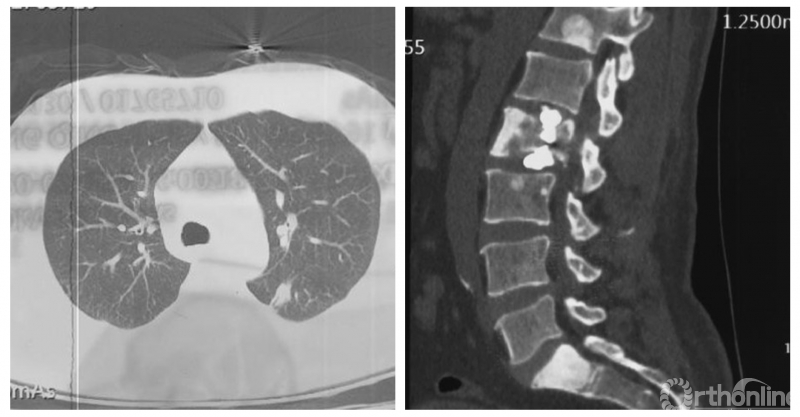

为进一步减少创伤,获得更好的综合疗效。骨采用经皮内固定的微创杂交技术,暨经皮内固定结合小切口分离手术,手术失血900ml,术后7天出院。

术中资料

手术视频:http://res.orthonline.com.cn/video/SSZH.mp4